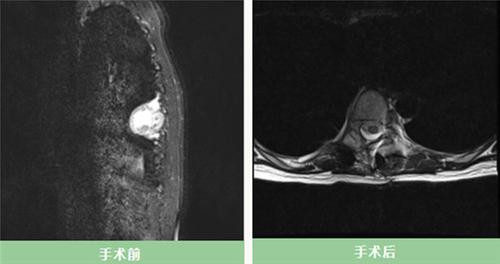

什邡市人民医院:髋关节的全面“翻修”,挑战与成功并存

王宇 陈远航

|

2024/08/16 15:57

2360点击